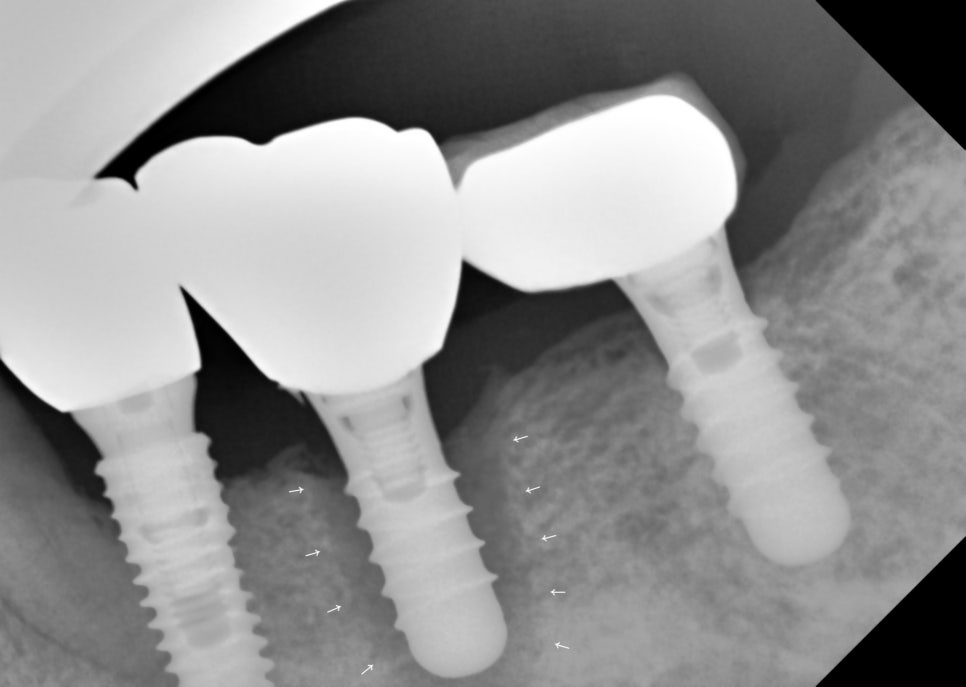

그런데 이렇게 임플란트 주위 염증이나

만성 잇몸 염증 (만성 치주질환, 치주염)으로

잇몸이 내려 앉은 경우

혹은 잇몸뼈가 녹아 없어진 경우에

바로 기둥을 심을 만한 뼈가

부족한 경우가 꽤 있습니다.

그림1. 임플란트 주위염 (임플란트 주변 어두운 부분)

그림2. (그림1)에서 임플란트 발치 후 뼈이식